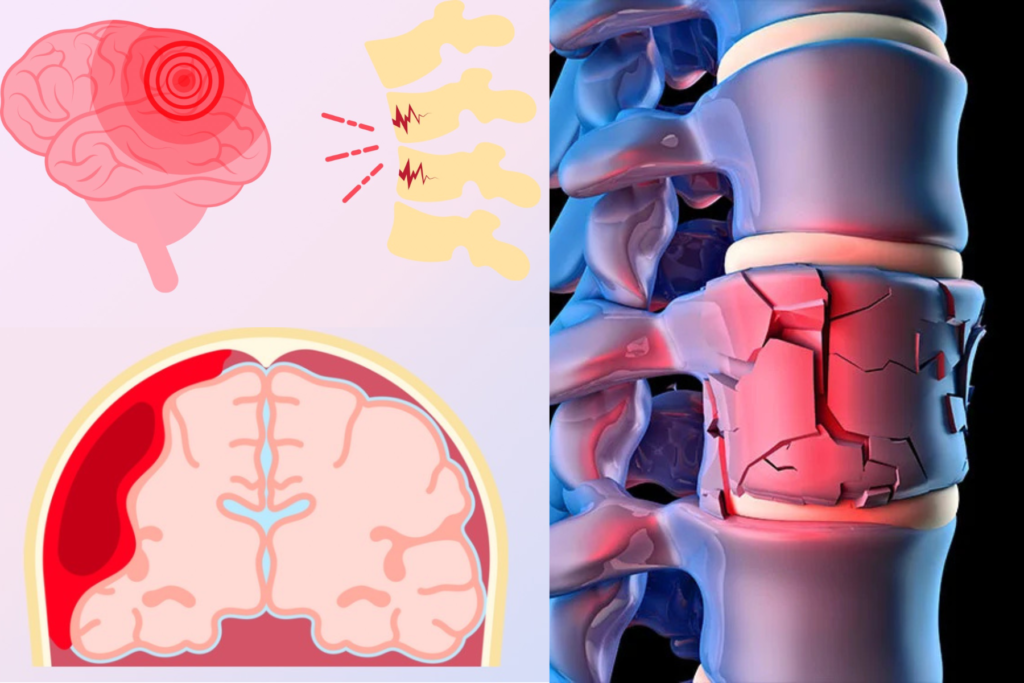

Brain & Spine Trauma Care

Prompt and precise management of neurological trauma is essential to prevent long-term disability.

Brain Injury Management: Surgical and non-surgical treatment of head injuries, management of intracranial bleeding and brain swelling, emergency and critical care.

Spine Trauma Management: Treatment of spinal fractures and dislocations, stabilization of spinal cord injuries, and surgical or minimally invasive fixation techniques.